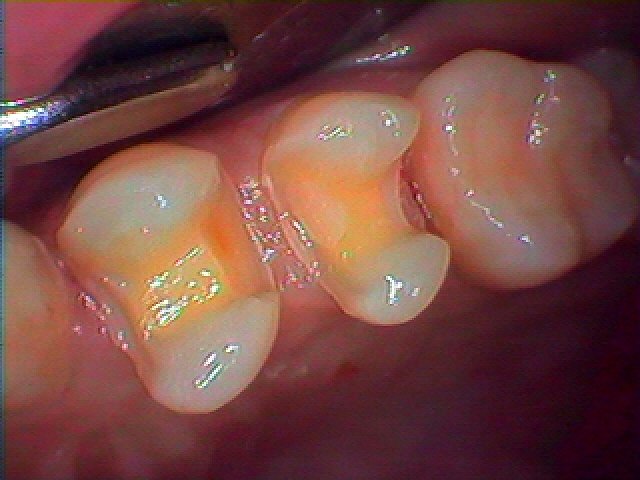

左上の4,5番の銀歯を外していきます

銀歯を外していきました